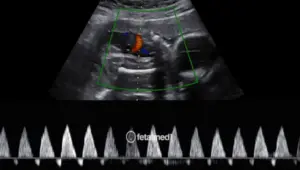

A cardiotocografia (CTG) é um exame que registra simultaneamente os batimentos cardíacos fetais e as contrações uterinas. É um dos principais métodos de avaliação do bem-estar fetal no terceiro trimestre da gestação.

O exame é simples, não invasivo e indolor. Sensores são colocados no abdômen materno e o registro é realizado por 20 a 40 minutos.